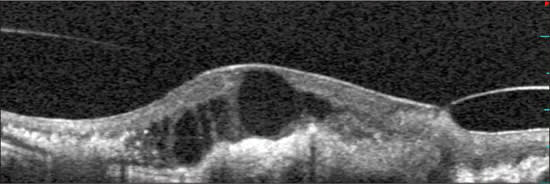

There is a difference between vitreomacular adhesion and vitreomacular traction (Figure 4). Actual vitreomacular traction was also more common in exudative macular degeneration. In eyes with exudative disease, there is a relationship between the location of the CNV complex and the vitreomacular adhesion. This suggests that the exudative process increases adhesion in close proximity.

Figure 4. Classification scheme of hyaloid adhesion and vitreomacular traction seen with spectral optical coherence tomography. Top: Eye with non-exudative age-related macular degeneration and drusenoid detachment: the hyaloid is partially attached over the macula, including the fovea. We considered this as a “no traction” configuration, since no distortion is visible on the retinal surface and the angle of insertion of the hyaloid onto the retina is not steep. Bottom: Eye with choroidal neovascularization. The persistence of hyaloid adhesion causes vitreomacular traction over the choroidal neovascularization complex: a focal distortion of the retinal profile is visible at the site of hyaloid attachment.